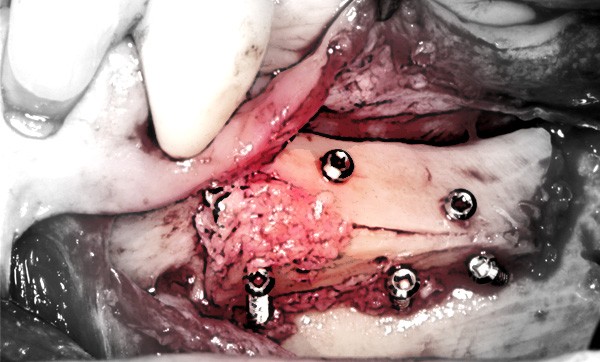

La chirurgie d’augmentation osseuse de la mandibule postérieure est exigeante, du fait de son anatomie et de sa vascularisation. La fermeture hermétique et sans tension des tissus mous au-dessus de la zone greffée constitue un paramètre critique pour une bonne cicatrisation. Ainsi, le tracé d’incision muqueux devra être choisi en fonction du type de greffe à réaliser (augmentation horizontale ou verticale) et de la technique d’augmentation utilisée (type de greffe, utilisation de biomatériaux ou de membranes).

En raison de son anatomie complexe et de son histologie tissulaire, les greffes d’augmentation osseuse à la mandibule sont des chirurgies difficiles. Quels que soient les matériaux ou techniques utilisés, les greffes osseuses de ce secteur sont les plus sujettes à des expositions prématurées. La prédictibilité des greffes osseuse verticales mandibulaires a beaucoup plus de variables que celles des greffes horizontales.

Un facteur clé dans la réussite de ces techniques horizontales et verticales est la promotion de la revascularisation par une gestion adaptée des tissus mous en fonction de la situation.